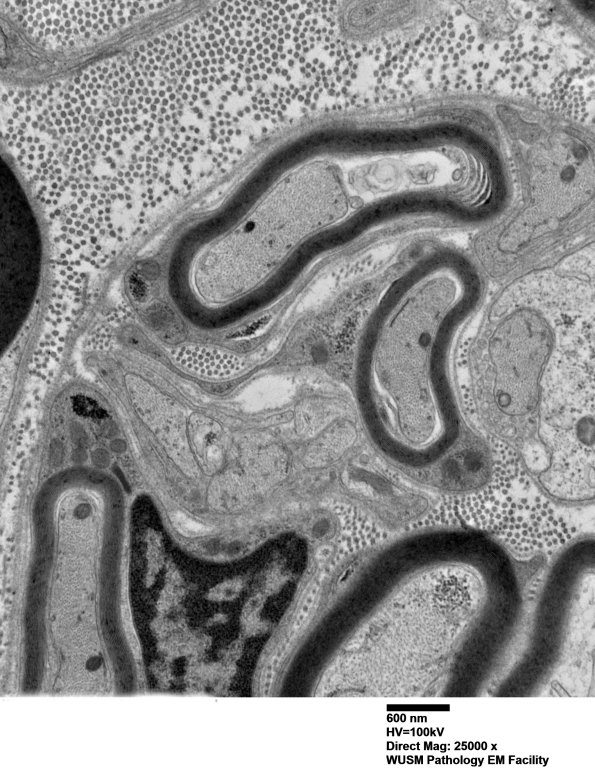

Multiple images of this cluster of immature, likely regenerative axons, collections of Schwann cell cytoplasm and small axons which represents pathologic alteration and not normal structures. (electron micrograph)